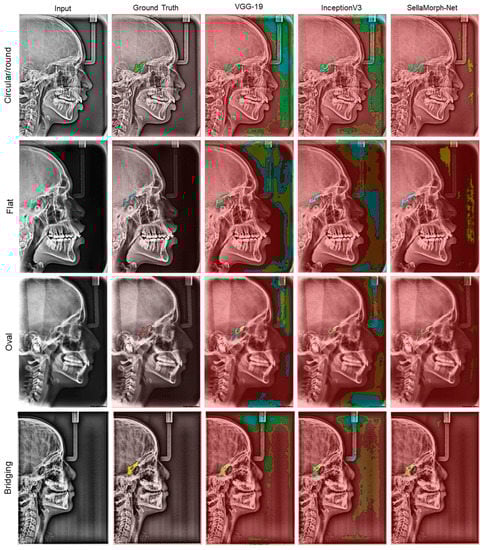

In order to assess the qualitative performance and efficacy of the suggested method, the study presents visual outcomes for the segmentation of regular, moderately altered, and complexly altered ST structures in Figure 8, Figure 9 and Figure 10. These structures were selected based on the cephalometric dataset’s complexity. In addition, the study compared the accuracy of our hybrid SellaMorph-Net model against VGG-19 and InceptionV3. The results demonstrated that while VGG-19 and InceptionV3 were able to provide an approximate ST type, they were unable to predict the detailed morphological structures of ST.

On the other hand, SellaMorph-Net predicted the ST types with high precision for all three dataset subgroups. Furthermore, the complex altered ST structure in Figure 10 was evaluated, and it was found that SellaMorph-Net predicted the edges of these complex altered categories with greater accuracy and smoothness than the other two models. Further, the proposed model accuracy is validated using 400 cephalometric dataset images available publicly, and the results show the significant performance of the proposed hybrid model in the discussion section (Table 7).

The figures presented in this study demonstrate the efficacy of the proposed method in segmenting complex non-linear structures of the ST in lat ceph radiographs. The segmentation was successful for various classes of ST, including bridging, circular, flat, and oval in severely anomalous structures, indicating its potential for clinical prognostics. Additionally, the segmentation of the Sella was conducted on a dataset that included regular and complex subgroups, allowing for the evaluation of dataset combinations. The study utilised statistical methods such as mean IoU (Jaccard Index) and Dice Coefficient (Equations (5)–(8)) to evaluate the performance of the proposed and pre-trained models. Furthermore, the accuracy and pixel-wise IoU of each architecture were compared with determine which performed better.

Figure 10. Qualitative results of VGG-19, InceptionV3, and proposed hybrid SellaMorph-Net on complex altered Sella Turcica subgroup dataset.